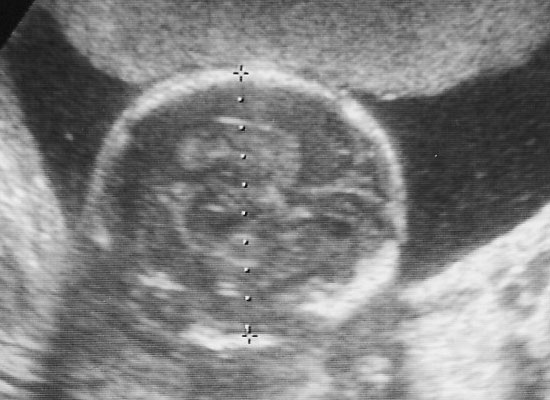

『胎のうがうっすらと確認出来る程度なんで、まだはっきりとわからない』と言われてたんですね。

しかしとりあえず、丸い粒は見えて着床してるって事はわかったんで、旦那には『育つかどうかわからんけどとりあえず出来てるっぽい』と説明しときました。

胎のうやら、心音は結構早めに確認出来てたんですけどね。

内視鏡写真は毎度いただけます。